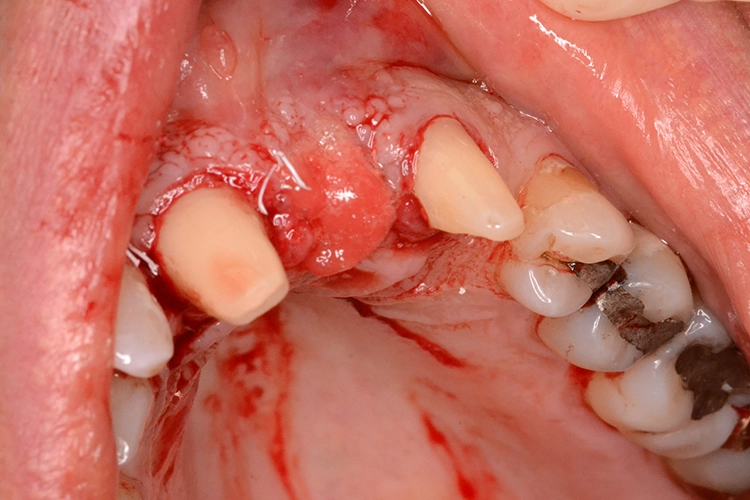

Im präoperativ angefertigten DVT (Abb. 3b und c) zeigte sich um die Wurzelspitze ein chronisches Entzündungsgeschehen, welches die vestibuläre Lamelle im apikalen Wurzelbereich des Zahnes 23 komplett aufgelöst hat. Da jedoch der Bereich direkt apikal von 23 nicht vom Geschehen betroffen war, fiel die Entscheidung zur Sofortimplantation auch, da der Patient blutverdünnende Medikamente einnehmen musste, welche durch Kombination von Extraktion und Implantation nur einmal abgesetzt werden mussten. In diesem Fall war aufgrund des Knochendefektes die Bildung eines Volllappens mit Entlastung unumgänglich.

Dr. Opitz

Anschließend wurde der Knochendefekt mit kortikospongiösem Knochengranulat aufgefüllt und mit einer langsam resorbierenden Kollagenmembran versorgt (Abb. 3e und f). Das OP-Gebiet musste im Anschluss aufgrund der Augmentation vollständig gedeckt werden (Abb. 3g).